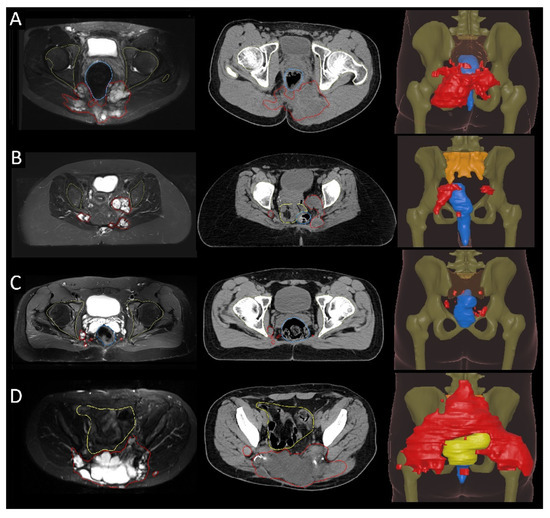

3.3. Postoperative Radiotherapy Planning Based on Recurrence Patterns